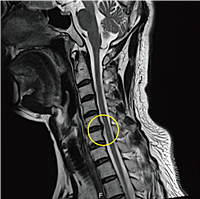

추간판 탈출이나 퇴행성 경추증, 경추관 협착증 등으로 척수가 압박되면 팔의 힘이 빠지는 증상이 나타날 수 있습니다. 양팔의 감각이 둔해지고 어지러움을 느끼는 경우에는 즉시 병원을 방문해야 합니다.

목디스크 치료는 비수술과 수술로 나뉩니다. 대부분의 경우 비수술 치료를 통해 증상이 개선될 수 있습니다. 물리치료, 약물치료, 도수치료 등이 일반적인 비수술 치료 방법이며, 증상이 호전되지 않으면 신경차단술 등의 주사치료를 고려할 수 있습니다.

심한 경우에는 수술적 치료가 필요할 수 있습니다. 수술 방법으로는 수핵성형술, 통증초래점 주사 치료, 추나요법 등이 있으며, 증상이 심각하고 일상생활이 어려운 경우 수술을 고려해야 합니다.